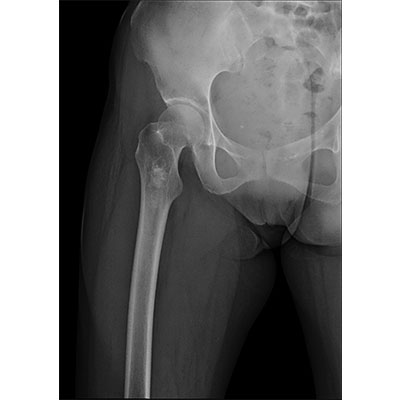

● 采用自主研發(fā)的技術(shù),在保證優(yōu)質(zhì)圖像的前提下,大大降低X射線劑量,用心呵護醫(yī)護工作者及患者的健康。

● 短曝光時間,便于老年人、兒童、殘疾人進行臨床拍攝。避免這類群體因不能有效控制身體運動等因素造成的運動偽影,提高攝片質(zhì)量及效率。